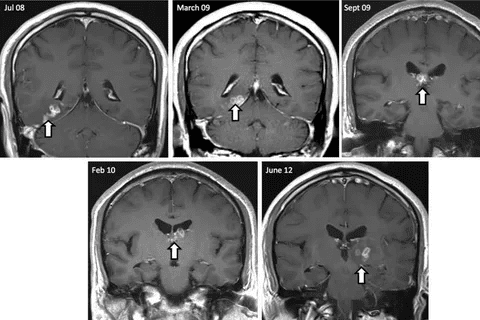

Imaging is key in finding brain lesions. MRI (Magnetic Resonance Imaging) and CT (Computed Tomography) scans are main tools. MRI spots soft tissue issues well, while CT scans are fast and used in emergencies.

MRI gives us clear brain pictures. It shows where, how big, and what kind of lesions are. It can tell if it’s a tumor, cyst, or inflammation. CT scans are great for finding bleeding, calcifications, and bone problems.

At times, watching and waiting is the best approach. This is true for small, benign lesions that don’t cause symptoms. Regular scans like MRI or CT help see if the lesion changes.